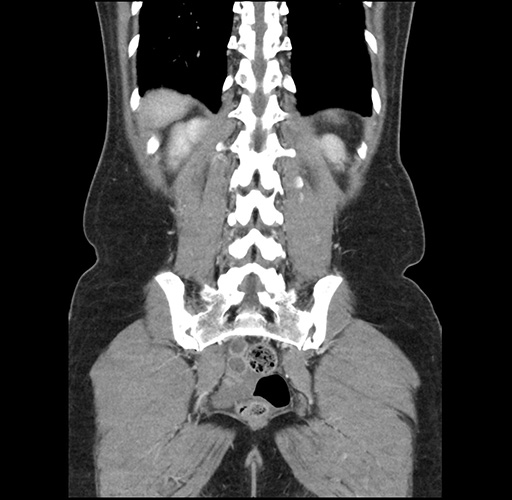

Imaging Analysis

Look through the patient's CT scan to identify any areas of concern for the necessary procedure.

Based on your CT findings, which issue(s) would give reason for "planned slowing down moment(s)" in this case?